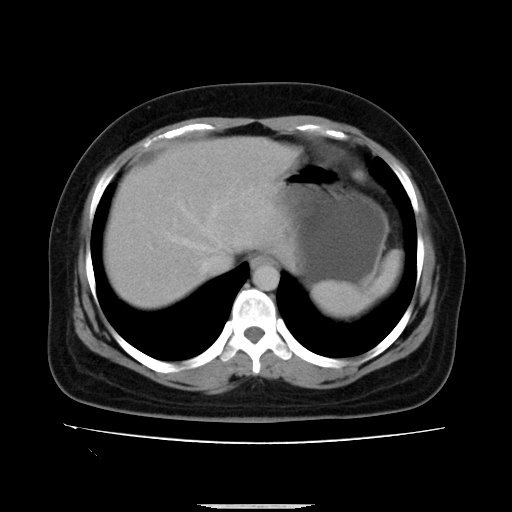

标题: CT14225:女性46岁。当地B超示肝内占位,来我院作CT检查。请 [打印本页]

标题: CT14225:女性46岁。当地B超示肝内占位,来我院作CT检查。请

速升速降,支持肝癌.脾体积增大,形态欠规整,请询问病史是否做过脾动脉栓塞.

速升速降,支持肝癌可能。

快进快出,符合肝癌表现-----------

肝内结节强化特点符合原发性肝癌表现,脾脏改变考虑为增大及先天发育所致。

动脉期病原灶明显强化高于肝密度且中央有无强化区,静脉期强化程度下降明显,延迟低于肝密度,考虑肝腺瘤可能性大,

肝内结节强化特点:快进快出符合原发性肝癌表现

此患者虽然符合快进的特点,却不符合快出的特点,因为门脉期几乎是等密度,不符合肝癌的增强表现,所以我考虑肝局灶性结节增生可能性大